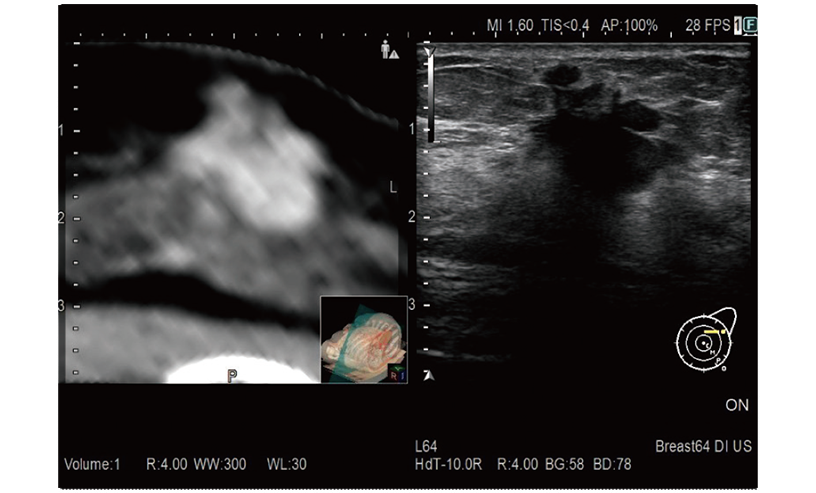

RVS is a function which fuses real-time ultrasound imaging with an MPR image created from the previously acquired CT, MRI or ultrasound volume data. RVS, a treatment supportting function by simultaneous display with other modalities, assists the positioning of treatment and the detection of small lesions that are difficult to find by ultrasound alone.

Provides simulation of single or multiple needle paths during navigation to a target with RVS. The positional relationship between the marked target and needle paths can be assessed in real time using the 3D body mark, reconstructed from the virtual CT volume data, with additional C-plane display orthogonal to the needle path.